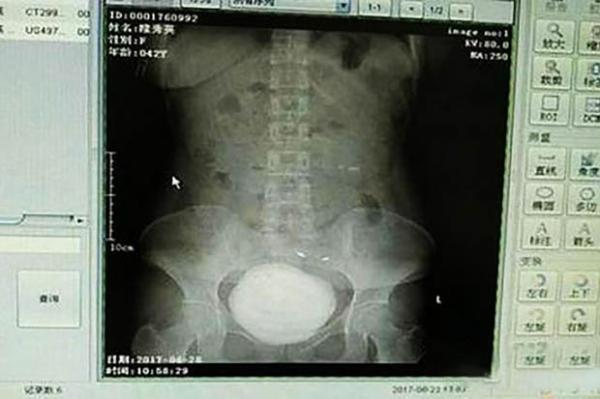

Một người phụ nữ Trung Quốc thấy mình đi tiểu ra máu liền tới bệnh viện khám. Các bác sĩ đã choáng khi phát hiện trong bàng quang của bà này có một 'quái vật" to như đá tảng. Hóa ra đó là một cục sỏi bàng quang đường kính tới 19cm.

Các bác sĩ tại bệnh viện Aksu First People đã tiến hành các bước chụp chiếu cơ thể cho cô Long và đã vô cùng kinh hoàng khi phát hiện ra rằng có một khối sỏi khổng lồ nằm trong bàng quang của cô.

Theo bác sĩ Liu, khối sỏi bàng quang trong cơ thể cô Long có đường kính lên tới 10cm và trọng lượng khoảng 760g, tương đương với kích thước và cân nặng của viên bi sắt.

"Khối sỏi này dường như đã ở trong cơ thể của cô ấy và phát triển trong nhiều năm nay nhưng không được phát hiện, nó chính là nguyên nhân của vấn đề mà cô ấy đang gặp phải", bác sĩ Liu cho biết.

Khối sỏi bàng quang trong cơ thể cô Long có đường kính lên tới 10cm.